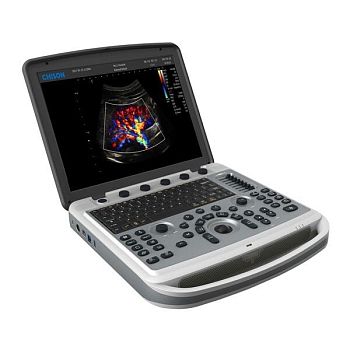

Клинические изображения

Технические характеристики

- CW - доплер

- MFI (Macro Fidelity Imaging - технология макро-точности)

- HPRF - Высокочастотный импульсный допплер

- Режим трапециевидного сканирования на линейных датчиках («виртуальный конвекс»)

- THI - тканевая гармоника

- Nanoview - адаптивный режим шумоподавления

- Freehand 3D - трехмерная реконструкция методом "свободной руки"

- Auto-fit - автоматическая оптимизация изображения

- Xbeam - многолучевое сложносоставное сканирование

- Auto IMT - автоматический расчет толщины комплекса интима-медиа с программой анализа

- Panoscope - панорамное сканирование

- Анатомический М-режим

- 4D-трехмерное сканирование в реальном времени